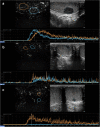

Background: Contrast-enhanced ultrasound (CEUS) is a sonographic technique that increases the diagnostic accuracy of ultrasound and color Doppler ultrasound (CDUS) when studying testicular abnormalities. However, its role in clinical practice is still debatable because there are no accepted standards regarding how and when this technique should be used for patients with testicular disease.

Results: Strong enhancement of neoplastic lesions (both benign and malignant) during CEUS aids in differential diagnosis with non-neoplastic lesions, which usually appears either nonenhanced or enhanced in a manner similar to that of the surrounding parenchyma. CEUS enhancement has a high predictive value in the identification of neoplastic lesions, whereas a similar or complete absence of enhancement may be interpreted as strong evidence of benignity, although there are exceptions. Literature on quantitative analysis is still scarce, though promising, particularly in distinguishing benign from malignant neoplasms. Furthermore, CEUS may be useful in many emergency situations, such as acute scrotum, blunt scrotal trauma, and focal infarction of the testis. Finally, CEUS can help increase the probability of sperm recovery in azoospermic males.